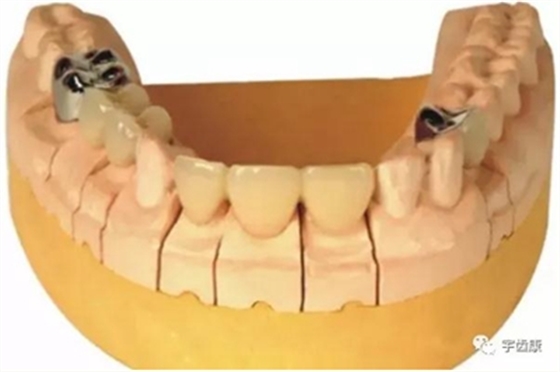

7. 共同就位道的調(diào)節(jié)

多個(gè)基牙時(shí)就位道的調(diào)節(jié)